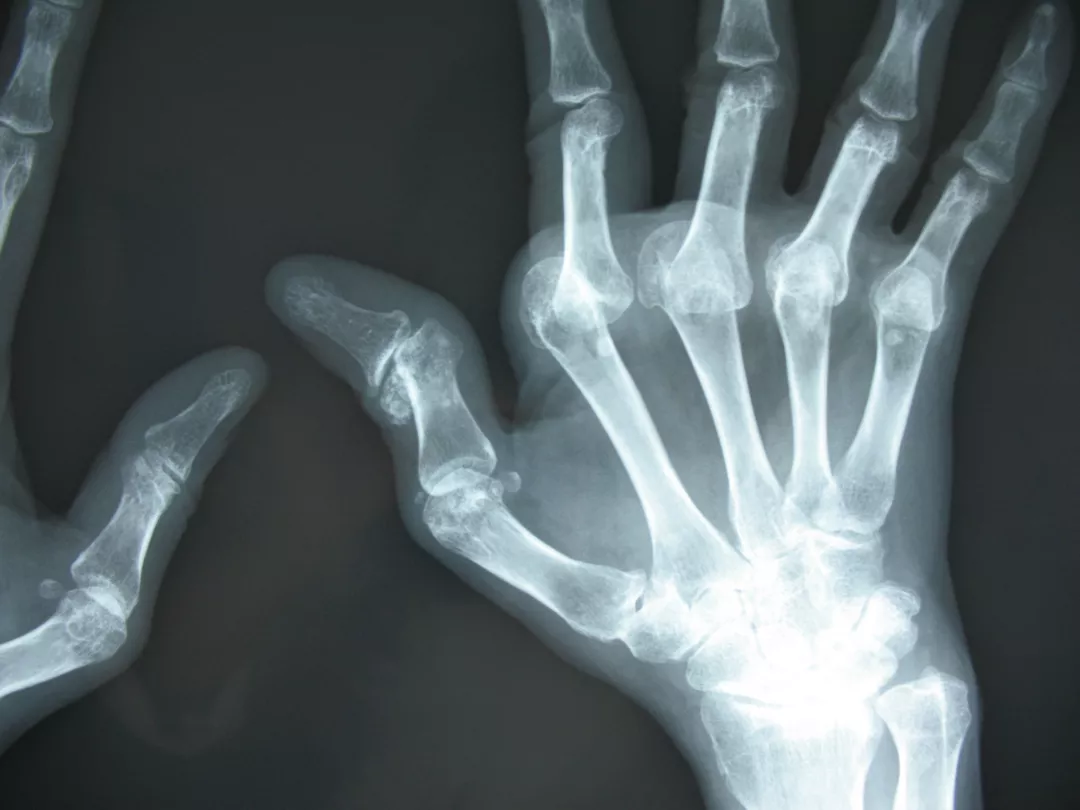

身体所見では手指関節炎、下腿浮腫、右頬部に紅斑を認めた。血液検査で抗核抗体陽性、抗DNA抗体高値、補体低下、尿たんぱく陽性、リウマチ因子陰性、抗CCP抗体陰性。手指関節X線では、2-5指中手指節間関節の掌側脱臼を認めるが、骨には異常を認めない(写真2)。関節超音波検査では、腱鞘滑膜炎を主体とする炎症を認めた(写真3)。尺側偏位や掌側亜脱臼は、関節リウマチの変形として有名であるが、全身性エリテマトーデスでも関節炎が強い症例では同様の変形を認めることがある。これをJaccoud関節炎と呼ぶが、強い亜脱臼や脱臼、腱拘縮による変形にも関わらず、骨破壊は認めないのが特徴である。本症例は、リウマチ因子陰性、抗CCP抗体陰性で、否定はできないが関節リウマチの可能性は低い。手指関節炎、抗DNA抗体上昇、補体低下、尿たんぱく陽性所見から、ループス腎炎を伴う全身性エリテマトーデスの再燃が疑われ、関節変形も、全身性エリテマトーデスによるJaccoud関節炎に起因すると診断した。

写真2